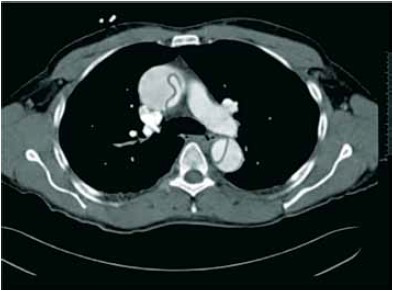

Após realização das medidas iniciais na sala de emergência, realizou uma tomografia de torax.